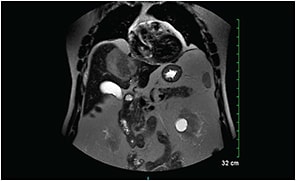

Referral to a tertiary medical center resulted in an MRI scan with identification of the large liver mass and four additional areas of enhancement in the patient’s liver (Figure 2, page 40). MRI of the brain and orbit was negative for space-occupying lesions.

Figure 2. MRI scan of the abdomen, showing the metastatic tumor in the liver.